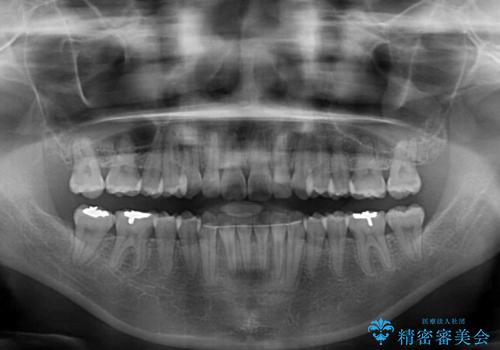

- 上下前歯のデコボコを気にして来院された患者様です。

デコボコを解消する過程で、歯列の拡大により口元が突出する可能性があったため、4本の親知らずを抜歯しておき、歯列全体が後方に移動するように設計し、インビザラインにて矯正治療を行うこととしました。

日々の装着時間をしっかりと守って治療の臨んでくださったため、治療前のシミュレーションに近い形で矯正治療を進めて行くことができました。